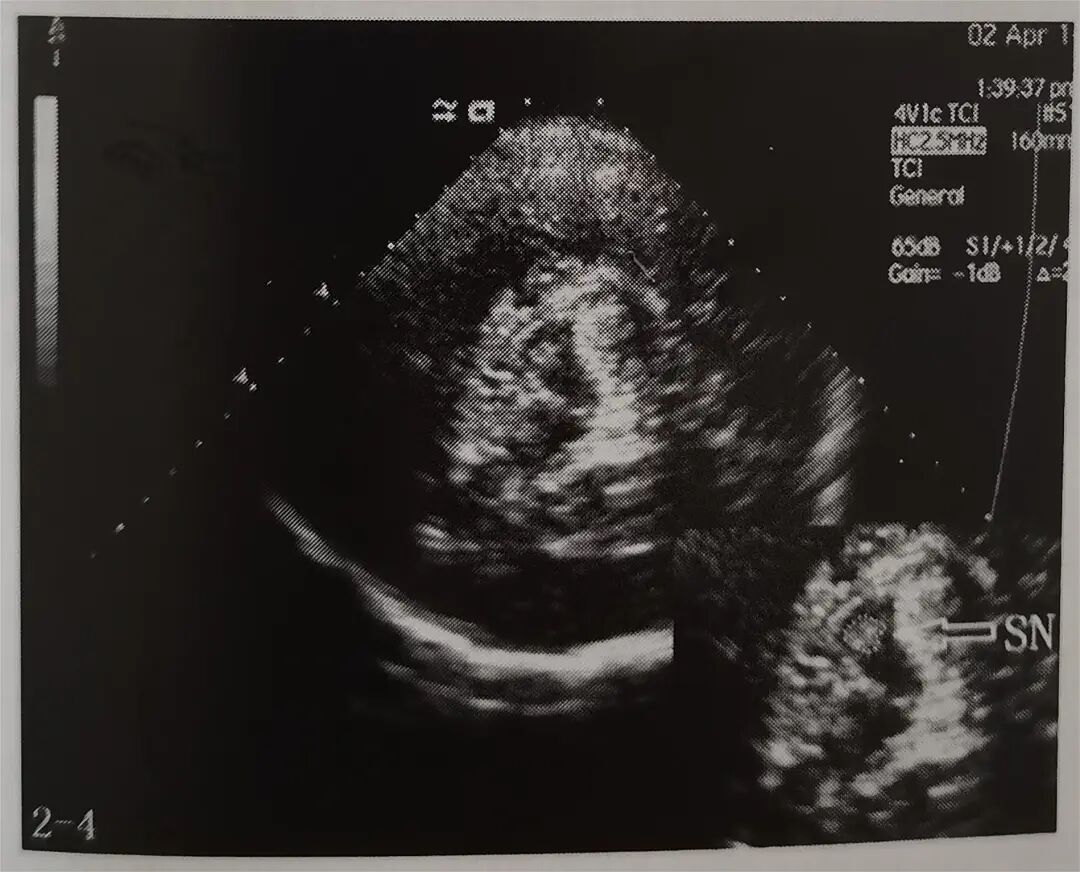

多年来,贵州航天医院各科室紧跟医学前沿,不断强技术、补短板,大力开展新技术、新项目,完成了许多高精尖、高难度、本地区“首例”的技术,填补了医院医疗技术空白,满足了群众日益增长的医疗需求。 复杂性双胎超声监护耗时耗力,技术难度大,风险高,为填补本地区复杂性双胎的超声监护技术空白,我院超声科在遵义市率先开展了此项技术,有效满足了双胎孕妇产检需求,保障了双胎新生儿的平安健康。 本期,我们将为大家带来超声科特色技术——复杂性双胎的超声监护。 案例分享 案例一 28岁的孕妇,自然受孕,怀有单绒毛膜双羊膜囊双胎(MCDA),在我院定期产检的过程中,孕32周超声检查发现两个胎儿的大脑中动脉血流流速(MCA-PSV)相差>0.7倍数的正常值(MoM),高度怀疑发生了双胎贫血红细胞增多序列征(TAPS)。为进一步明确诊断,产科立即组织超声科、手术室、新生儿科等科室进行多学科会诊(MDT),诊断为:双胎贫血红细胞增多序列征(TAPS),在征得孕妇及其家属的同意后,决定提前分娩,及时保障了两名胎儿的生命和健康。 双胎大脑中动脉血流 双胎贫血红细胞增多序列征(TAPS) 案例二 一名26岁的孕妇,是完全双角子宫,且为左侧子宫妊娠,怀有单绒毛膜双羊膜囊双胎(MCDA),一直在我院规律产检,孕16周时,超声检查发现双胎生长不一致,体重相差超过25%,考虑子宫畸形合并早发选择性胎儿宫内生长受限。孕妇在咨询相关上级医院专家后,得到减胎的建议,又前来我院咨询,在我院超声科和产科的合作下,查阅了大量文献、认真评估检查报告后,建议孕妇继续双胎妊娠。在规律、严密的超声监护下,双胎除体重差异外未出现严重胎儿并发症,在34周进行了分娩,截至目前,新生儿生长发育均正常。 胎儿生长曲线及子宫畸形三维重建 出生时体重差异 十月龄时 案例三 一名30岁的孕妇,自然受孕,怀有单绒毛膜双羊膜囊双胎(MCDA),在孕22周时超声检查发现双胎发生了选择性胎儿宫内生长受限,遂转诊到上级医院拟行胎儿镜治疗,但在行治疗的前一天,较小的胎儿在宫内发生死亡,在充分与孕妇及家属沟通后,要求继续妊娠,在定期规范的产检下,严密监测胎儿生长发育及胎儿颅脑MRI影像,最终在孕37周时通过剖宫产分娩,目前新生儿生长发育情况良好。 双胎之一胎死宫内(右图) 贵州航天医院自2021年开展复杂性双胎的超声监护以来,已服务大量双胎孕妇,集齐了所有单绒毛膜双羊膜囊双胎(MCDA)并发症病例,由经验丰富的超声医师进行此项检查,产科专业团队进行双胎的规范化监护和分娩,并与重庆医科大学附属第一医院建立了转诊通道,能够及时获得该院专家的指导和支持,为广大孕产妇提供优质、全面的医疗保障。 点击跳转贵州航天医院便民服务电话 什么是复杂性双胎的超声监护 “双胎”被称为产科之王,单绒毛膜双胎则为王中王,主要是因为单绒毛膜双羊膜囊双胎(MCDA)两胎儿共用一个胎盘,胎盘中存在血管吻合。 双胎妊娠的产前筛查及诊断主要依靠超声,相对于单胎妊娠,双胎妊娠并不是单胎检查的重复,双胎妊娠尤其是复杂性双胎的超声诊断更为重要的是关注双胎间循环的关联,双胎间生理及病理改变的相互影响,双胎间血流动力学监测及双胎间差异比较。 超声如何诊断 复杂性双胎并发症 在孕14周以前,超声要明确双胎的绒毛膜性:是单绒毛膜(MC)还是双绒毛膜(DC);孕10周前,可以通过孕囊的个数确定绒毛膜性;孕11周—14周,可以通过胎儿的性别、双胎之间隔膜的厚度、双胎儿分隔膜处胎盘的形态等来区分绒毛膜性。 双绒毛膜双胎的管理和单胎差不多,基本不需要增加超声检查的频次。单绒毛膜的管理相对谨慎,按照国际国内指南规范,单绒毛膜双胎自第16周起,每两周对双胎儿进行生长发育评估及血流检查。 复杂性双胎的超声监护,对超声医生技术要求较高,孕早期需对双胎的绒毛膜性进行精确判断;产科医生根据绒毛膜性制定孕期的产检计划;超声医生掌握胎儿宫内情况,及时与产科医生沟通,精确了解胎儿宫内安危后制定合适的治疗方案,给出适当的终止妊娠时机;复杂性双胎一般都面临早产的风险,所以新生儿团队的专业保障不可或缺,降低新生儿出生后的并发症及提高新生儿生活质量。复杂性双胎的较好妊娠结局,是通过孕期超声科、产科紧密合作,及新生儿出生后新生儿科管理多学科团队合作所获得的。 贵州航天医院超声科专家团队 吴艳辉 超声科 学科带头人 主任医师 专业擅长:从事超声诊断工作约30年,对心血管、小器官超声、超声引导下介入等具有丰富的临床经验。 骆科美 超声科 副主任医师 专业擅长:从事超声诊断工作33年,对胎儿心脏及颅脑、妇产超声诊断、盆底超声等诊断具有丰富的临床经验。 胡大海 超声科 副主任医师 专业擅长:从事超声工作17年,对心血管、外周血管、浅表器官超声诊断等具有丰富的临床经验。 刘 敏 超声科 副主任医师 专业擅长:从事超声诊断工作20余年,对妇产科超声、心脏血管超声诊断具有丰富的临床经验。 贵州航天医院超声科简介 贵州航天医院超声科配备多种超声检查设备(飞利浦彩超(IU-22、IU-Elite、HD11、Q5、Q7),迈瑞超声I9、DC-6、DC-8、GE-E8及床旁机,彩色超声诊断仪等),设有心血管诊室、妇产科诊室、腹部诊室、绿色通道、浅表小器官等检查室。 • ✦ 专科特色 ✦ • 四肢血管超声检查、双胎产前筛查及超声监护、超声造影检查技术、介入超声临床应用、经颅脑实质超声辅助筛查诊断帕金森病、女性性早熟超声诊断、盆底超声检查等。 NT超声检查 超声介入引导 肝脏超声造影 甲状腺造影 颅脑超声帕金森辅助检查 乳腺超声造影 上肢动静脉造瘘超声检查 双胎超声筛查 下肢血管超声检查 右心造影 • ✦ 诊疗范围 ✦ • 科室业务覆盖腹部、泌尿、妇科、产科(常规、NT筛查、III级筛查超声检查及高危妊娠监护)、成人心脏、外周血管、浅表器官(包含甲状腺、乳腺、阴囊、眼睛等)、颅脑(小儿颅脑、成人颅脑)、小儿肺超、造影、盆底、腹直肌、肌骨神经等检查及各种介入引导。